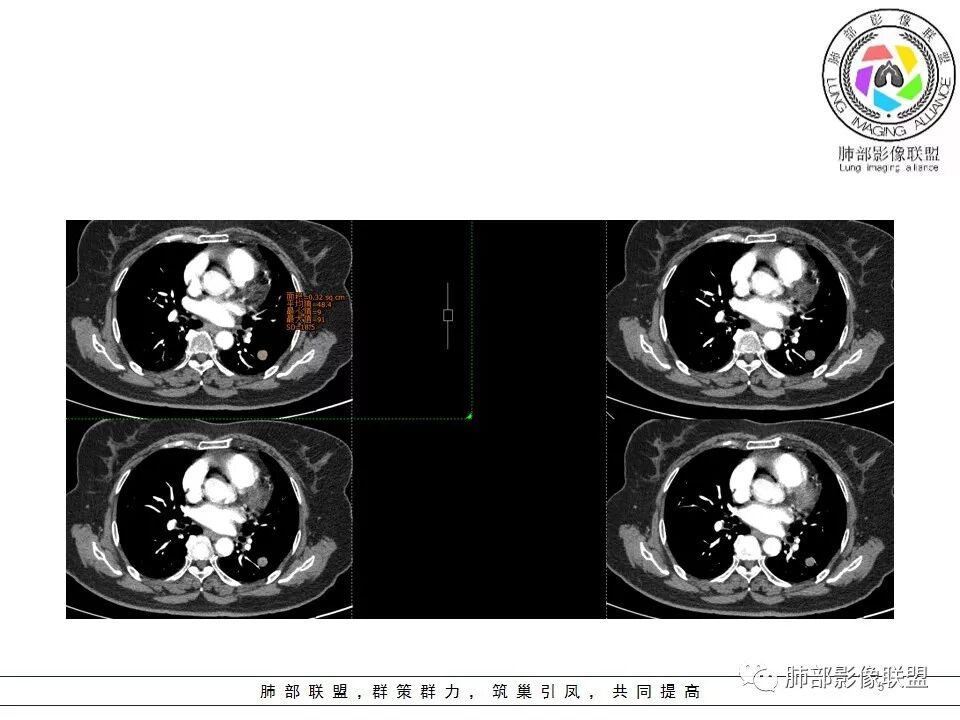

南边分析

南边 :

血管贴边征一般是有前提的

孤立结节,类圆形,边缘光滑,周围干净

与支气管有关吗?好像显示不明显

与血管的关系?

局部稍推压变

对比同级别血管稍增粗

密度尚均匀

CT值46H

增强67HU

动脉期弱一些,后期强化明显一些

动脉期边缘斑点状、结节状强化为主

后期趋向于均匀强化

动脉期测量区域——中央,不是强化区域

其实强化还算是中度,幅度超过20HU

支持良性

PSP可能 错构瘤待排

病理结果

错构瘤